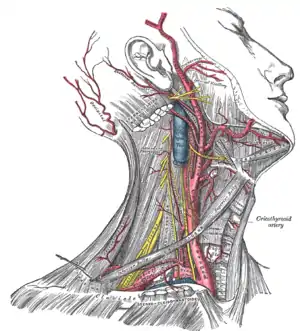

Blood, lymph and nerve supply

Blood supply

Blood circulates from the upper systemic loop originating at the aortic arch, and includes: the brachiocephalic artery, left common carotid artery and left subclavian artery. The head and neck are emptied of blood by the subclavian vein and jugular vein.

The brachiocephalic artery or trunk is the first and largest artery that branches to form the right common carotid artery and the right subclavian artery. This artery provides blood to the right upper chest, right arm, neck, and head, through a branch called right vertebral artery. The right and left vertebral artery feed into the basilar artery and upward to the posterior cerebral artery, which provides most of the brain with oxygenated blood. The posterior cerebral artery and the posterior communicating artery are within the circle of Willis.

The left common carotid artery divides to form the: internal carotid artery (ICA) and an external carotid artery (ECA). The ICA supplies the brain. The ECA supplies the neck and face.

The left subclavian artery and the right subclavian artery, one on each side of the body form the internal thoracic artery, the vertebral artery, the thyrocervical trunk, and the costocervical trunk. The subclavian becomes the axillary artery at the lateral border of the first rib. The left subclavian artery also provides blood to the left upper chest and left arm.